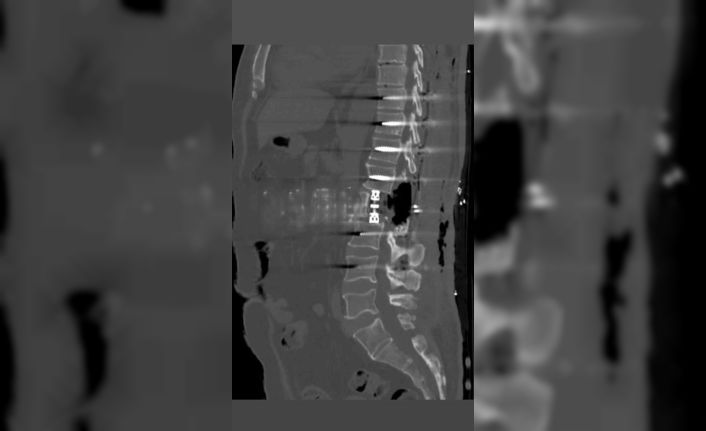

Bayburt Devlet Hastanesinde omurga bölgesindeki tümörler yapılan korpektomi işlemiyle alındı. Omurganın bir kısmının cerrahi olarak çıkarılması işlemi olan korpektomi ameliyatı Op.Dr Aziz Kaan Erçandırlı ve Op.Dr Ali Emre Özer tarafından başarılı bir şekilde yapıldı.

Bayburt Devlet Hastanesine belli başlı şikayetlerle başvuran hastaya korpektomi ameliyatı yapılarak, hastanın tümörleri temizlendi. Hastanın bel omurundaki enfeksiyon temizlendikten sonra kafes ve enstrüman sistemi ile sabitleme yapıldı. Beyin ve Sinir Cerrahisi Uzmanları Op.Dr Aziz Kaan Erçandırlı ve Op.Dr Ali Emre Özer tarafından yapılan operasyonla, hasta sağlığına kavuştu.